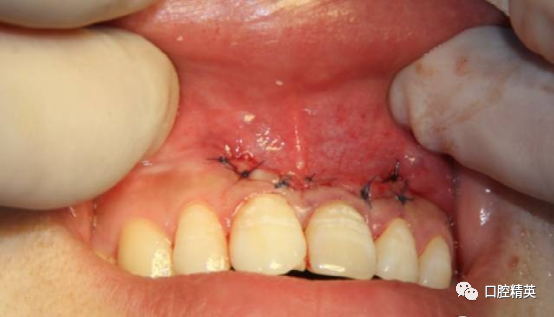

患者,女,31岁。于我院行21根管治疗。21呈生理动度。与邻牙参照略有变色。治疗数周无急性症状,但偶有不适。21唇侧根尖区有膨隆感,扪诊(+),质软,局部牙龈略红肿。转诊时口内照

缝合完成。塞治剂塞治,局部加压。